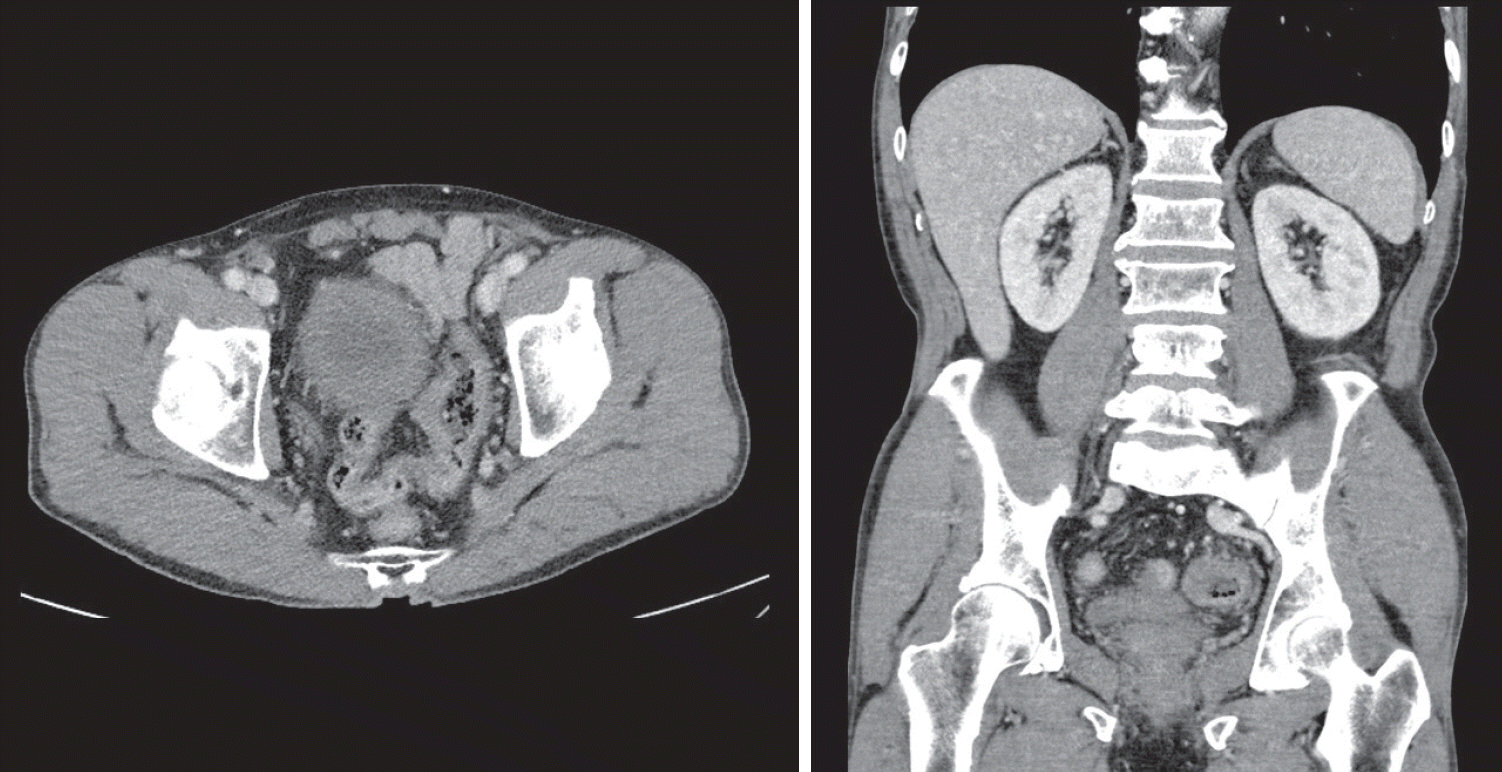

Figure 1.

Routine computed tomography (CT) showing thickening of the sigmoid colon wall.

A 70-year-old male underwent sigmoidoscopy after a routine computed tomography (CT) examination, which showed thickening of the sigmoid wall (Fig. 1). Sigmoidoscopy revealed a colonic ulcer, and a biopsy was performed. The lesion was identified as a tubular adenoma; therefore, the patient was referred to the gastroenterology department for repeat biopsy and additional tests. The patient’s medical history included high blood pressure and alcoholic hepatitis. His social history showed that he drank 0.5-1.0 bottle of soju daily and was never a smoker. Information regarding his family history was excluded from the study. The patient had no gastrointestinal symptoms such as abdominal pain or diarrhea, and physical examination findings were unremarkable. Although the biopsy showed a tubular adenoma, the initial colonoscopy indicated that the gross margin of the ulcer was irregularly shaped (Fig. 2), raising suspicion for malignancy. Therefore, despite being asymptomatic, the patient was informed, and another colonoscopy was performed 2 months later. The follow-up examination revealed a scarred sigmoid ulcer located 30 cm from the anal verge, which seemed to have improved compared with the previous findings. Re-biopsy demonstrated features consistent with a simple ulcer (Fig. 3). Accordingly, we concluded that this was a benign colonic ulcer with an inflammatory and ischemic cause rather than cancer, and a follow-up CT scan was sche-duled 1 month later. At the follow-up visit 1 month later, the patient complained of abdominal discomfort after eating for a week, which had not occurred before. He denied having fever, chills, nausea, or vomiting. A subsequent abdominal CT scan showed an approximately 9-cm cavitary lesion abutting the sigmoid colon and urinary bladder dome in the small intestine (Fig. 4). This was accompanied by diffuse nodular omentomesenteric infiltration and peritoneal thickening with small ascites. Based on these findings, the patient was suspected to have a malignant tumor, such as scirrhous carcinoma, inflammatory bowel disease, peritoneal carcinomatosis, or peritonitis, and was referred to a surgeon for surgical treatment. The patient was hospitalized immediately. On admission, the patient complained of abdominal discomfort after eating, and mild generalized abdominal tenderness was noted on physical examination. He was hemodynamically stable. Laboratory testing revealed high white blood cell count of 11.45 × 103/μL (normal range, 4.0-10.0 × 103/μL) with a differential of 67.6% neutrophils (normal range, 38.0-75.0), normal hemoglobin of 16.1 g/dL (normal range, 13.0-17.0), normal platelet count of 151 × 103/μL (normal range, 150-400 × 103/μL), and slightly elevated C-reactive protein level of 7.69 mg/L (normal range, 0.0-5.0). Serum electrolyte and kidney function test results were normal. On the 3rd day of hospitalization, the patient underwent laparoscopic small bowel resection. Immunohistochemical analysis of the resected tissue showed positive staining for CD3, CD4, CD8, CD56, and CAM 5.2 (epithelial marker), and a negative staining for CD10, CD20, CD21, and CD30 (Fig. 5). Histopathological evaluation revealed infiltration by small- to medium-sized T-cell with prominent epitheliotropism, consistent with MEITL. The final diagnosis was MEITL, involving the sigmoid colon, urinary bladder, and peritoneum. Postoperatively, the patient developed persistent ileus with progressive ab-dominal distension and loss of bowel passage, necessitating a second emergency surgery on the 20th day of hospitalization. On the 25th day of hospitalization, the Hemovac drainage became purulent, blood pressure decreased, and the patient went into shock; therefore, a third emergency surgery was performed under the suspicion of bowel perforation. On the 45th day of hospitalization, the patient died of refractory septic shock, presumed to be a complication of intestinal perforation.

Figure 4.

Subsequent abdominal computed tomography (CT) showing an approximately 9-cm cavitary lesion in the small intestine, abutting the sigmoid colon and urinary bladder dome.